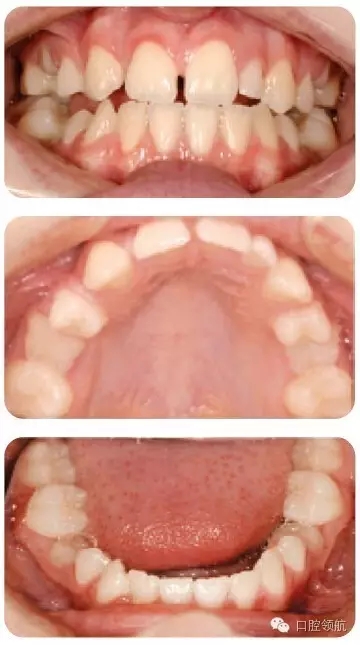

圖2.19中的III類病例有1顆過(guò)小的UL2, UR2和所有的第二前磨牙先天缺失,第二乳

磨牙滯留但預(yù)后不佳,治療方案是什么?

圖2.19

為了調(diào)整切牙III類關(guān)系,考慮擴(kuò)開間隙修復(fù)UR2和過(guò)小的UL2。所有低的第二乳磨牙拔除并關(guān)閉間隙。